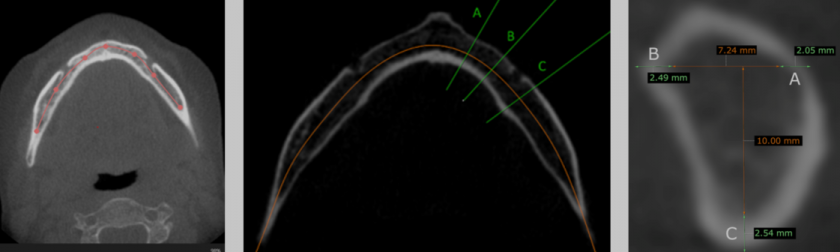

Ir apmācīts un validēts modulārs dziļais neirona tīkls, pamatā izmantota ResNet-101 arhitektūra. Tīkls sastāv no trim secīgiem dziļās apmācības modeļiem klasifikācijas un diviem regresijas uzdevumu risināšanai. Pirmais spēj atlasīt nepieciešamo apakšžokļa kaula griezumu KSDT attēlos aksiālā griezumā, kur vislabāk redzama foremen mentale. Tīkla apmācības precizitāte 98.85% (39 epohas), validācijas precizitāte 93.99% (35 epohas). Otrs veic apakšžokļa kaula griezumus pēc iepriekš definētiem attālumiem, iegūstot apakšžokļa šķērsgriezuma laukuma attēlus. Trešais veic apakšžokļa kortikālā kaula biezumu mērījumus.

SCOPUS indeksētā žurnālā Tomography tiek publicēts pētījums, kura mērķis bija mērķis izstrādāt modulāru dziļu neironu tīklu osteoporozes riska noteikšanai, balstoties mutes, sejas un žokļu 3D-KSDT CBCT izmeklējumiem un novērtēt tā spēju osteoporozes detektēšanas prognozēšanā.